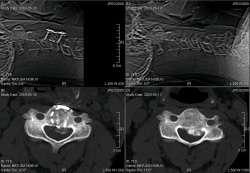

CT画像術前と術後もいただいてきましたのでUPします

クリックしてくだされば拡大表示されます。